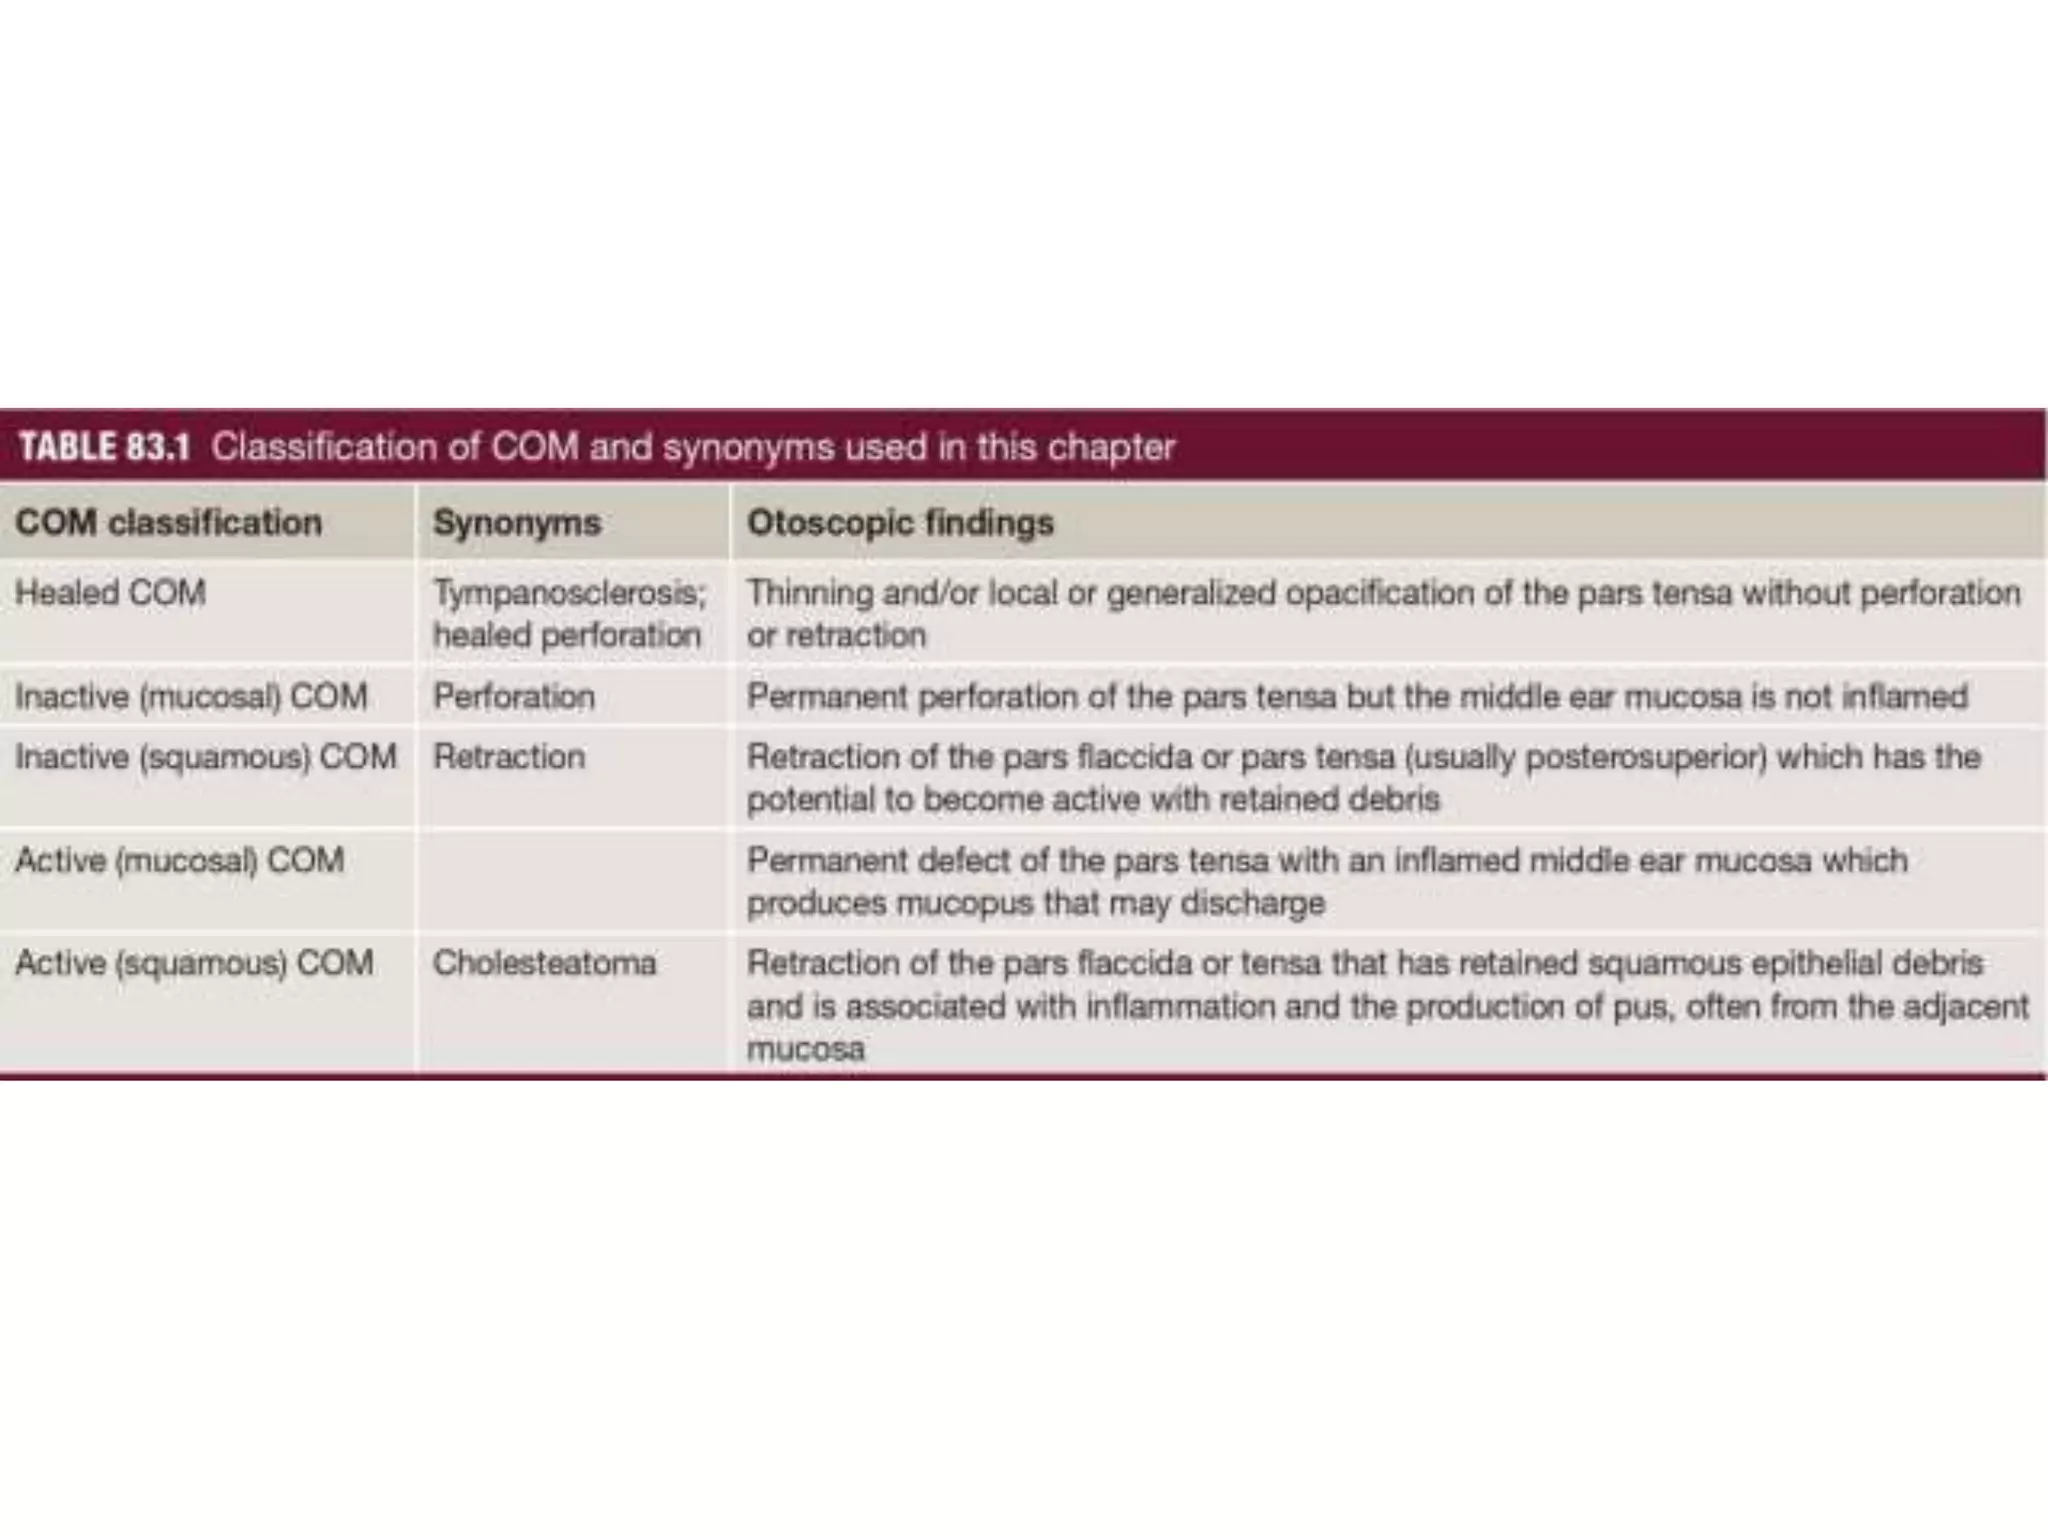

Chronic otitis media is a chronic inflammation of the middle ear and mastoid cavity that presents with recurrent ear discharge through a perforated eardrum. It has several subtypes depending on the state of the eardrum perforation and epithelium. It can be caused by prior acute otitis media, genetics, environment, eustachian tube issues, gastroesophageal reflux disease, craniofacial abnormalities, or immune deficiency.